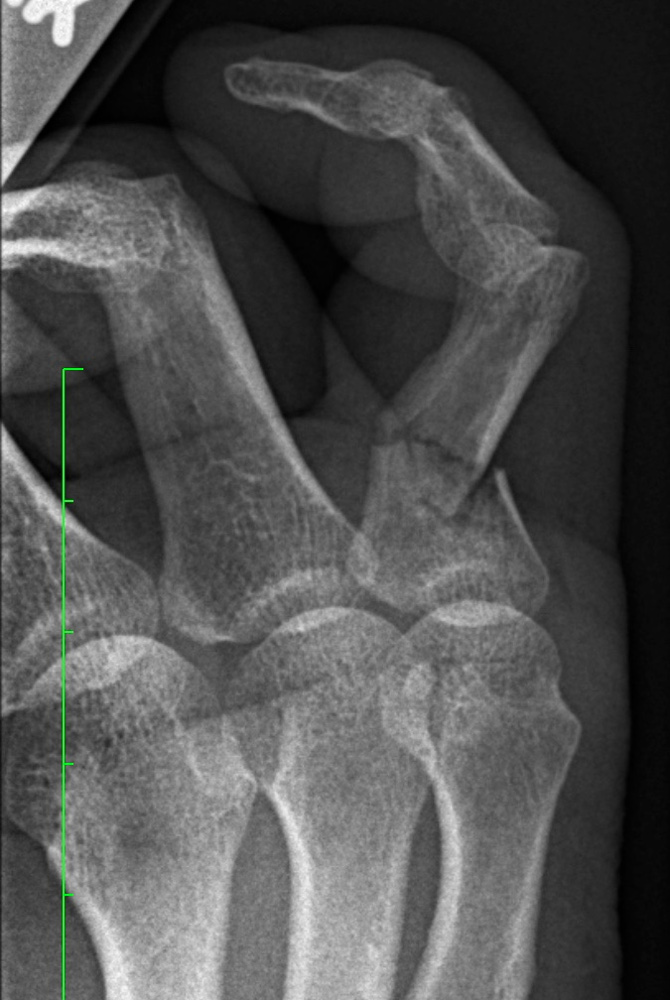

About the broken pinky

I broke my pinky on March 28, 2019 while doing an end sprint along the river houses near Dunster house. There is a dominant lonely tree there with a square shape root, hence square root over I fell over. The pinky was indeed in a terrible shape. Some nerve also got stuck because it did not hurt. But it looked not good. The technical description of the doctor was "continued angulated intra-articular fracture of the proximal phalanx of the 5th finger" It is true that I was referred to Mt Auburn Emergency. It is also true that I got charged again 30 dollars co-payment, but there was fortunately a lovely lady there whom I could convince that I already payed my 30 dollars before at HUHS (lovingly called Huuuuuhhh!s by the students). I indeed had met a cook there who told me that he had bled there for 3 hours. At the hospital, they indeed could already rectify a bit of the finger as otherwise, I would not have fit into the splint. It is true that each surgeon visit was again 30 dollars co-payment. I had to cut short the first appointment myself as I had a teaching commitment later. You can not assume that a doctor visit takes only 90 minutes. During the second visit, the pinky was linearized. The hand surgeon did it without actually needing to cut, it was a bit like molding (of course with a completely numbed up hand). He could not have done it better. No, nobody ever said "that is fucked up". The language of doctors is much more sophisticated (as you can see in the report of my doctor):